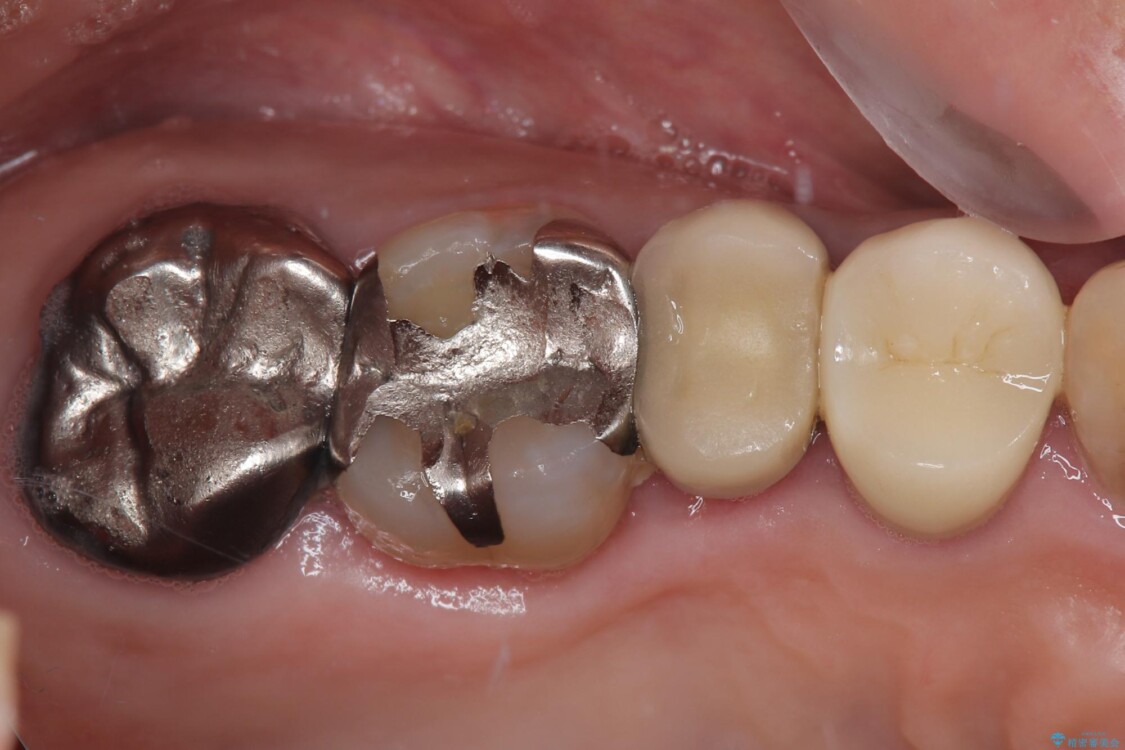

「以前治療した歯の被せものが外れてしまった」とのことで、右上の小臼歯の被せもの脱離を主訴に来院されました。

診察の結果、被せもの(クラウン)だけでなく、土台(コア)ごと外れてしまっている状態でした。根管治療済みの歯ではありますが、今回患者様のご希望により、根管治療の再治療は行わず、補綴処置のみを行う方針となりました。

治療前

• 自然な美しさと強度を両立!右上小臼歯の被せもの脱離に対する審美補綴治療 治療前画像